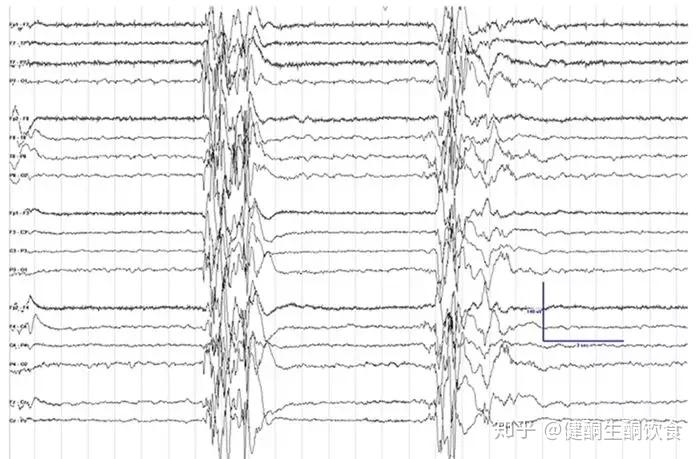

大田原综合征控制不了?试试生酮饮食治疗新方案

知名专家北京大学第一医院大田园综合征的治疗原则与一般的癫痫相似